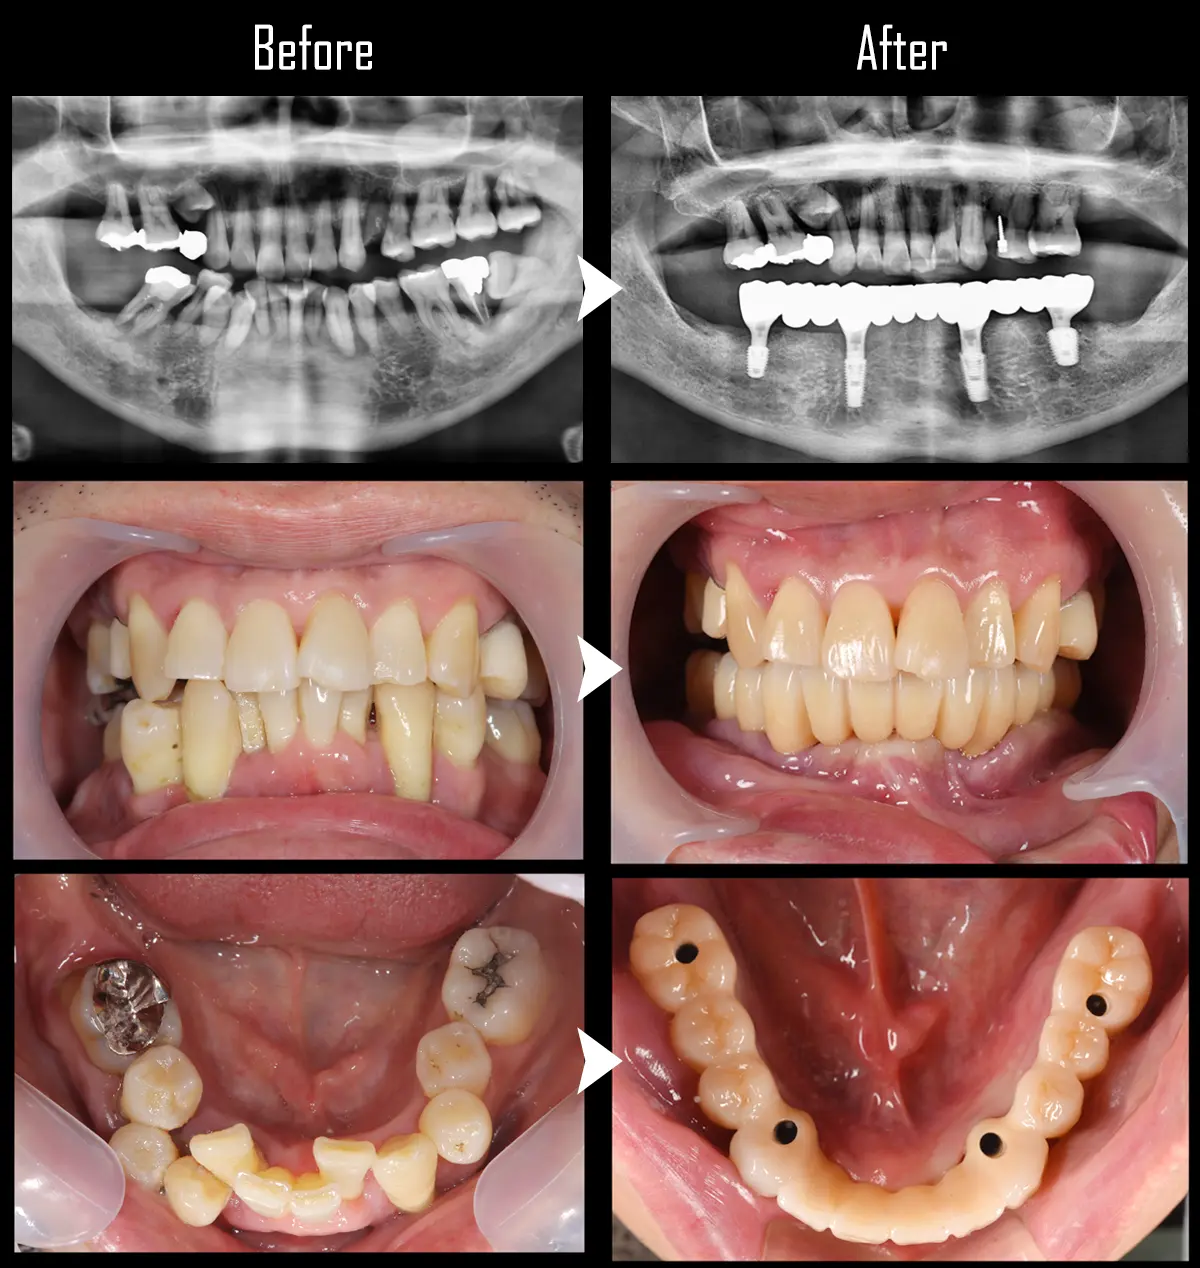

CASE:All-on-4とインプラントブリッジ

症例All-on-4(オール・オン・フォー)

主訴 奥歯がなく、前歯がすいてきたので治したい。

治療内容 上顎はAll-on-4(オール・オン・フォー)治療し、下顎はIMPBr(4本+2本ポンティック)で治療。

標準費用(自費) 上顎:440万円

下顎:319万円